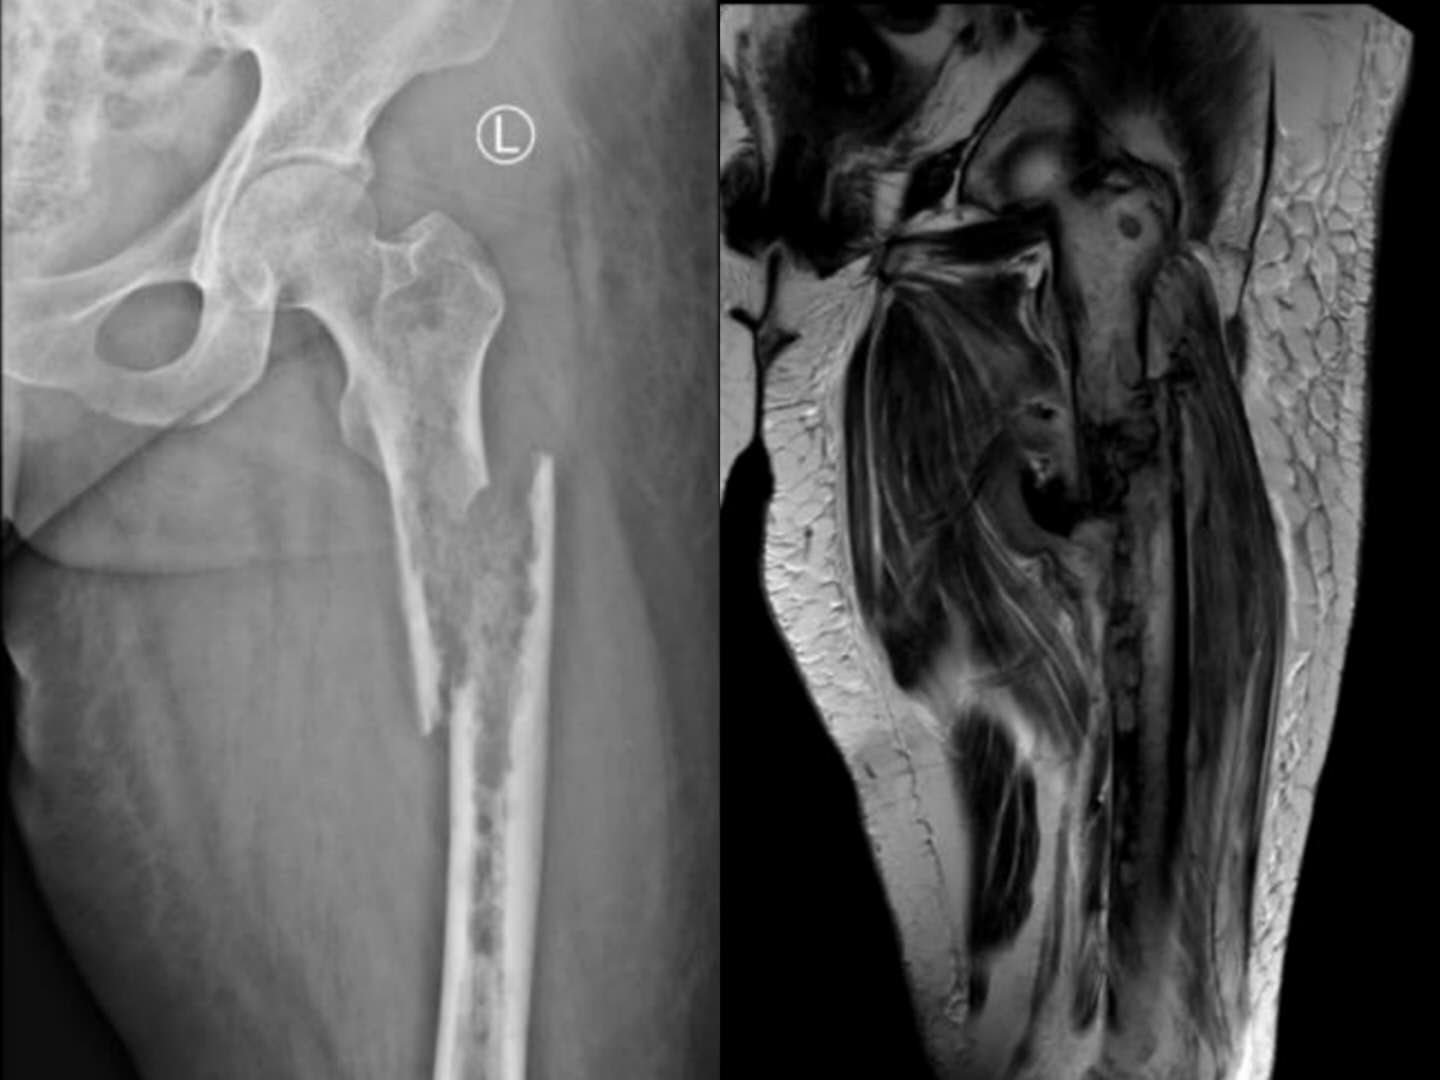

第一例患者女性,48岁,因“左大腿疼痛2月余,疼痛突然加重伴肿胀、畸形、活动障碍5天”入院。查体见痛苦病容,左大腿上端明显肿胀,呈屈曲、外旋、短缩畸形,左大腿中上段压痛明显,皮温升高,可触及骨擦感,左下肢活动障碍。初步诊断为左股骨病理性骨折。左股骨X线提示:左侧股骨近端虫蚀样骨质破坏并骨折,局部软组织密度改变。CT提示:左侧股骨上端广泛虫蚀状骨质破坏,中上段为著,周围软组织肿胀,考虑左侧股骨恶性骨肿瘤并病理性骨折。全身骨显像:左侧股骨中上段代谢异常增高伴软组织肿块,结合MRI考虑恶性骨肿瘤继发病理性骨折。后行穿刺活检,病理提示:符合转移性肺腺癌;(左侧远端髓腔肿物)见腺癌组织。由于患者非常痛苦,后并发下肢静脉血栓,其家属强烈要求手术,经我院医护对其全身严格评估并妥善处理下肢静脉血栓后,术前多学科讨论认为符合手术适应症,遂顺利行瘤段切除,人工假体置换重建术,髋关节囊及股骨上端重要肌肉附着点均使用laser韧带重建,历时3小时余。术后患者剧痛、烦躁、失眠等症状消失,活动明显增加,护理方便,医患双方对疗效非常满意,为后续治疗创造了有利条件。

术前X片图及核磁共振显示